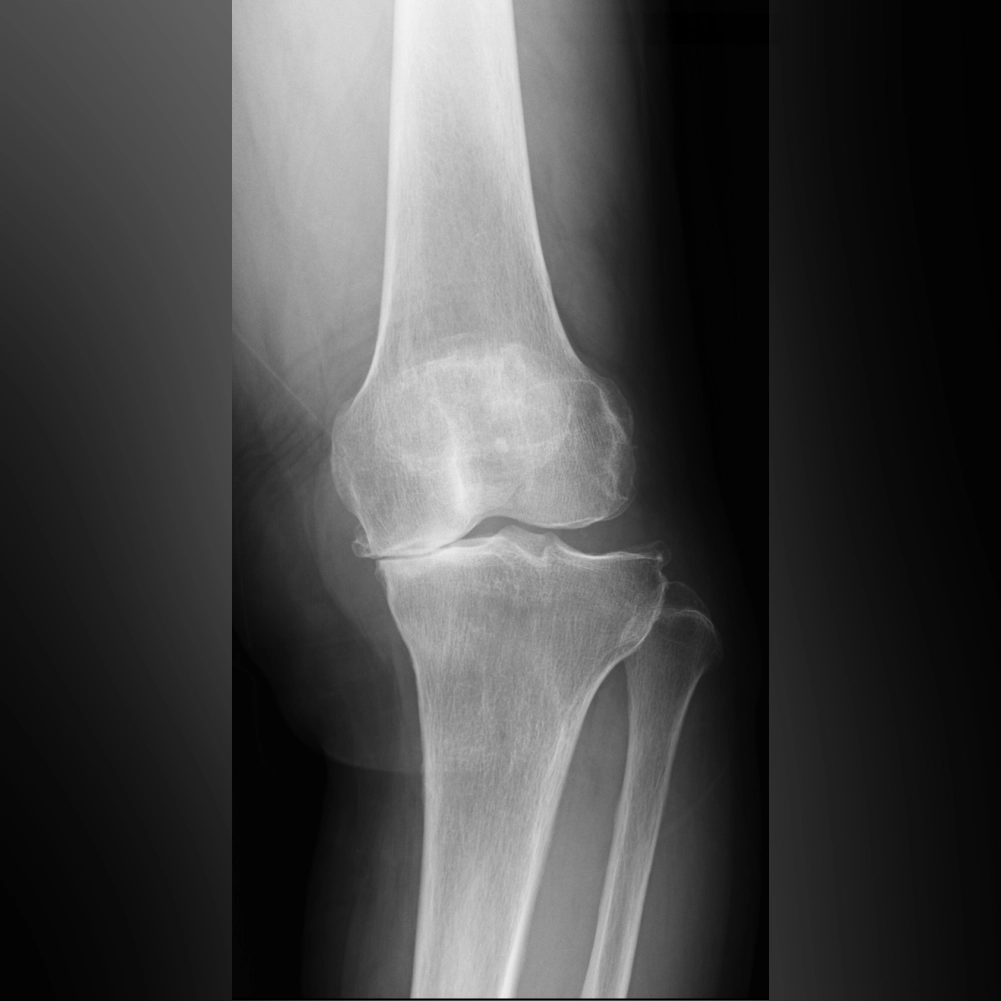

中期のレントゲンでは、内側関節の隙間がほとんどなくなります。この段階では、内側の軟骨が完全に失われ、大腿骨と脛骨が直接ぶつかっている状態です。低い椅子から立ち上がる際にゴリゴリという音がしたり、骨表面に髪の毛ほどの細いひび(微小骨折)が生じて強い痛みを感じるようになります。この中期変形性関節症の時期になると、痛みのために歩くのがつらくなる方が多くなります。

中期以降になると、痛み止めの薬を常用する方も増えてきます。痛みとは、ひざが脳に“骨が割れた”と知らせるシグナルであり、脳はそれを受けて修復のための炎症反応を起こし、血液を送って自己修復を始めます。ところが、痛み止めでそのシグナルを抑えたまま歩き続けると、関節の変形が進行して末期に至ることがあります。